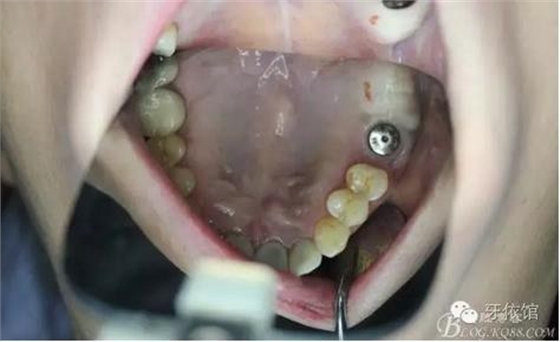

術后6個月口內(nèi)照